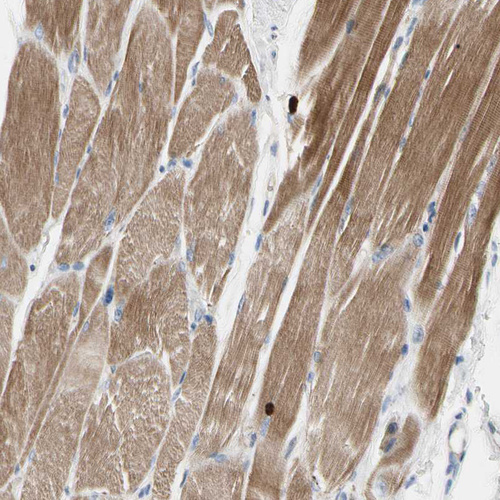

Immunohistochemical staining of human skeletal muscle shows moderate cytoplasmic positivity in myocytes.